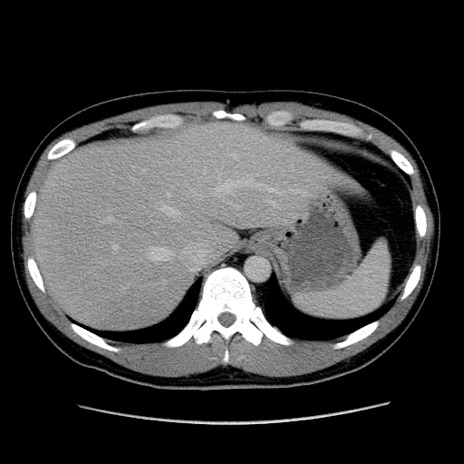

症例4(横断像)

【症例】30歳代男性

【主訴】腹痛、嘔吐

【現病歴】昨晩から突然の腹痛あり、その後嘔吐、軟便も出現。腹痛が改善しないため救急搬送となる。2日前にしめ鯖の食事歴あり。

【身体所見】意識清明、苦悶様、BP 135/90mmHg、BT 35.7℃、腹部:平坦、やや硬、心窩部〜臍部に自発痛、圧痛あり、筋性防御+、反跳痛-

【データ】WBC 8100、CRP 0.57